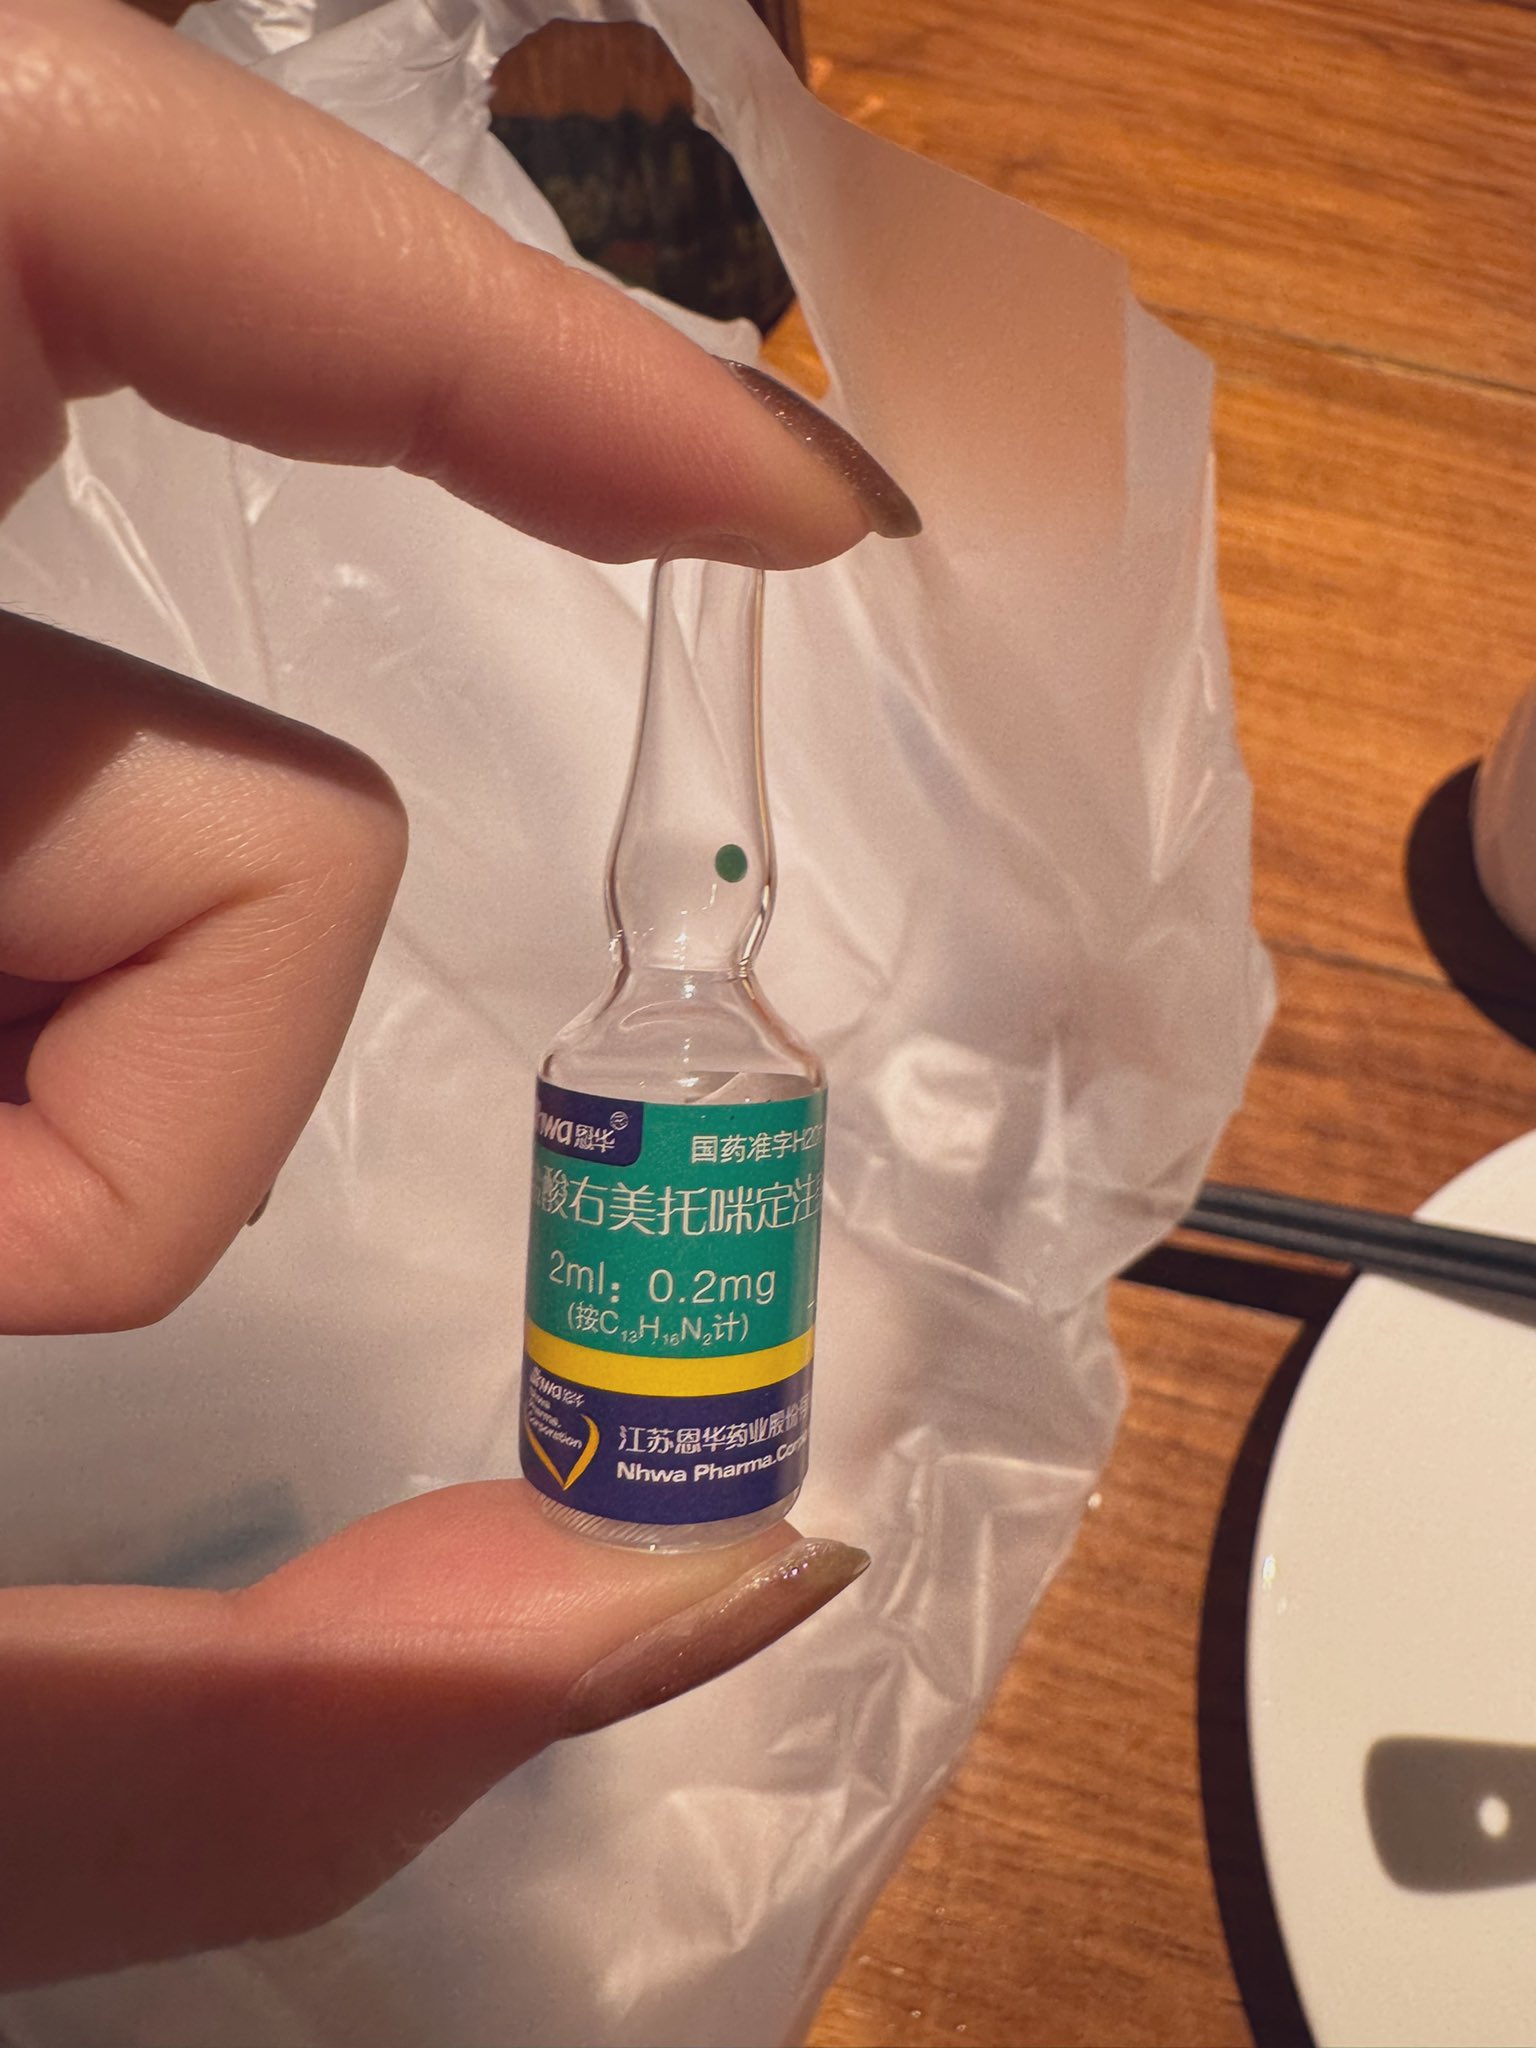

对于药物过量引起的中枢神经系统副作用,有一些不常见或常见的药物来控制症状。

评论区欢迎补充 https://t.co/7S4tGVDEM5

炽烈已极 @AnIncandescence纳洛酮:可用于阿片类药物过量(可获取的上市药品)需舌下给药,因肝脏首过代谢口服时利用度很低;效果持续30-90min;亦可用于酒精中毒的促醒等,但谨慎使用。

氟马西尼:苯二氮卓类药物拮抗剂,解毒剂,包括对z类药物有效;似乎没有上市药品

炽烈已极 @AnIncandescence阿托品:抗胆碱能药物(副交感神经阻断药),类似的还有东莨菪碱,苯海拉明,吩噻嗪类抗精神病药等。

可用于反制胆碱能药物过量(如多奈哌齐,石杉碱甲)